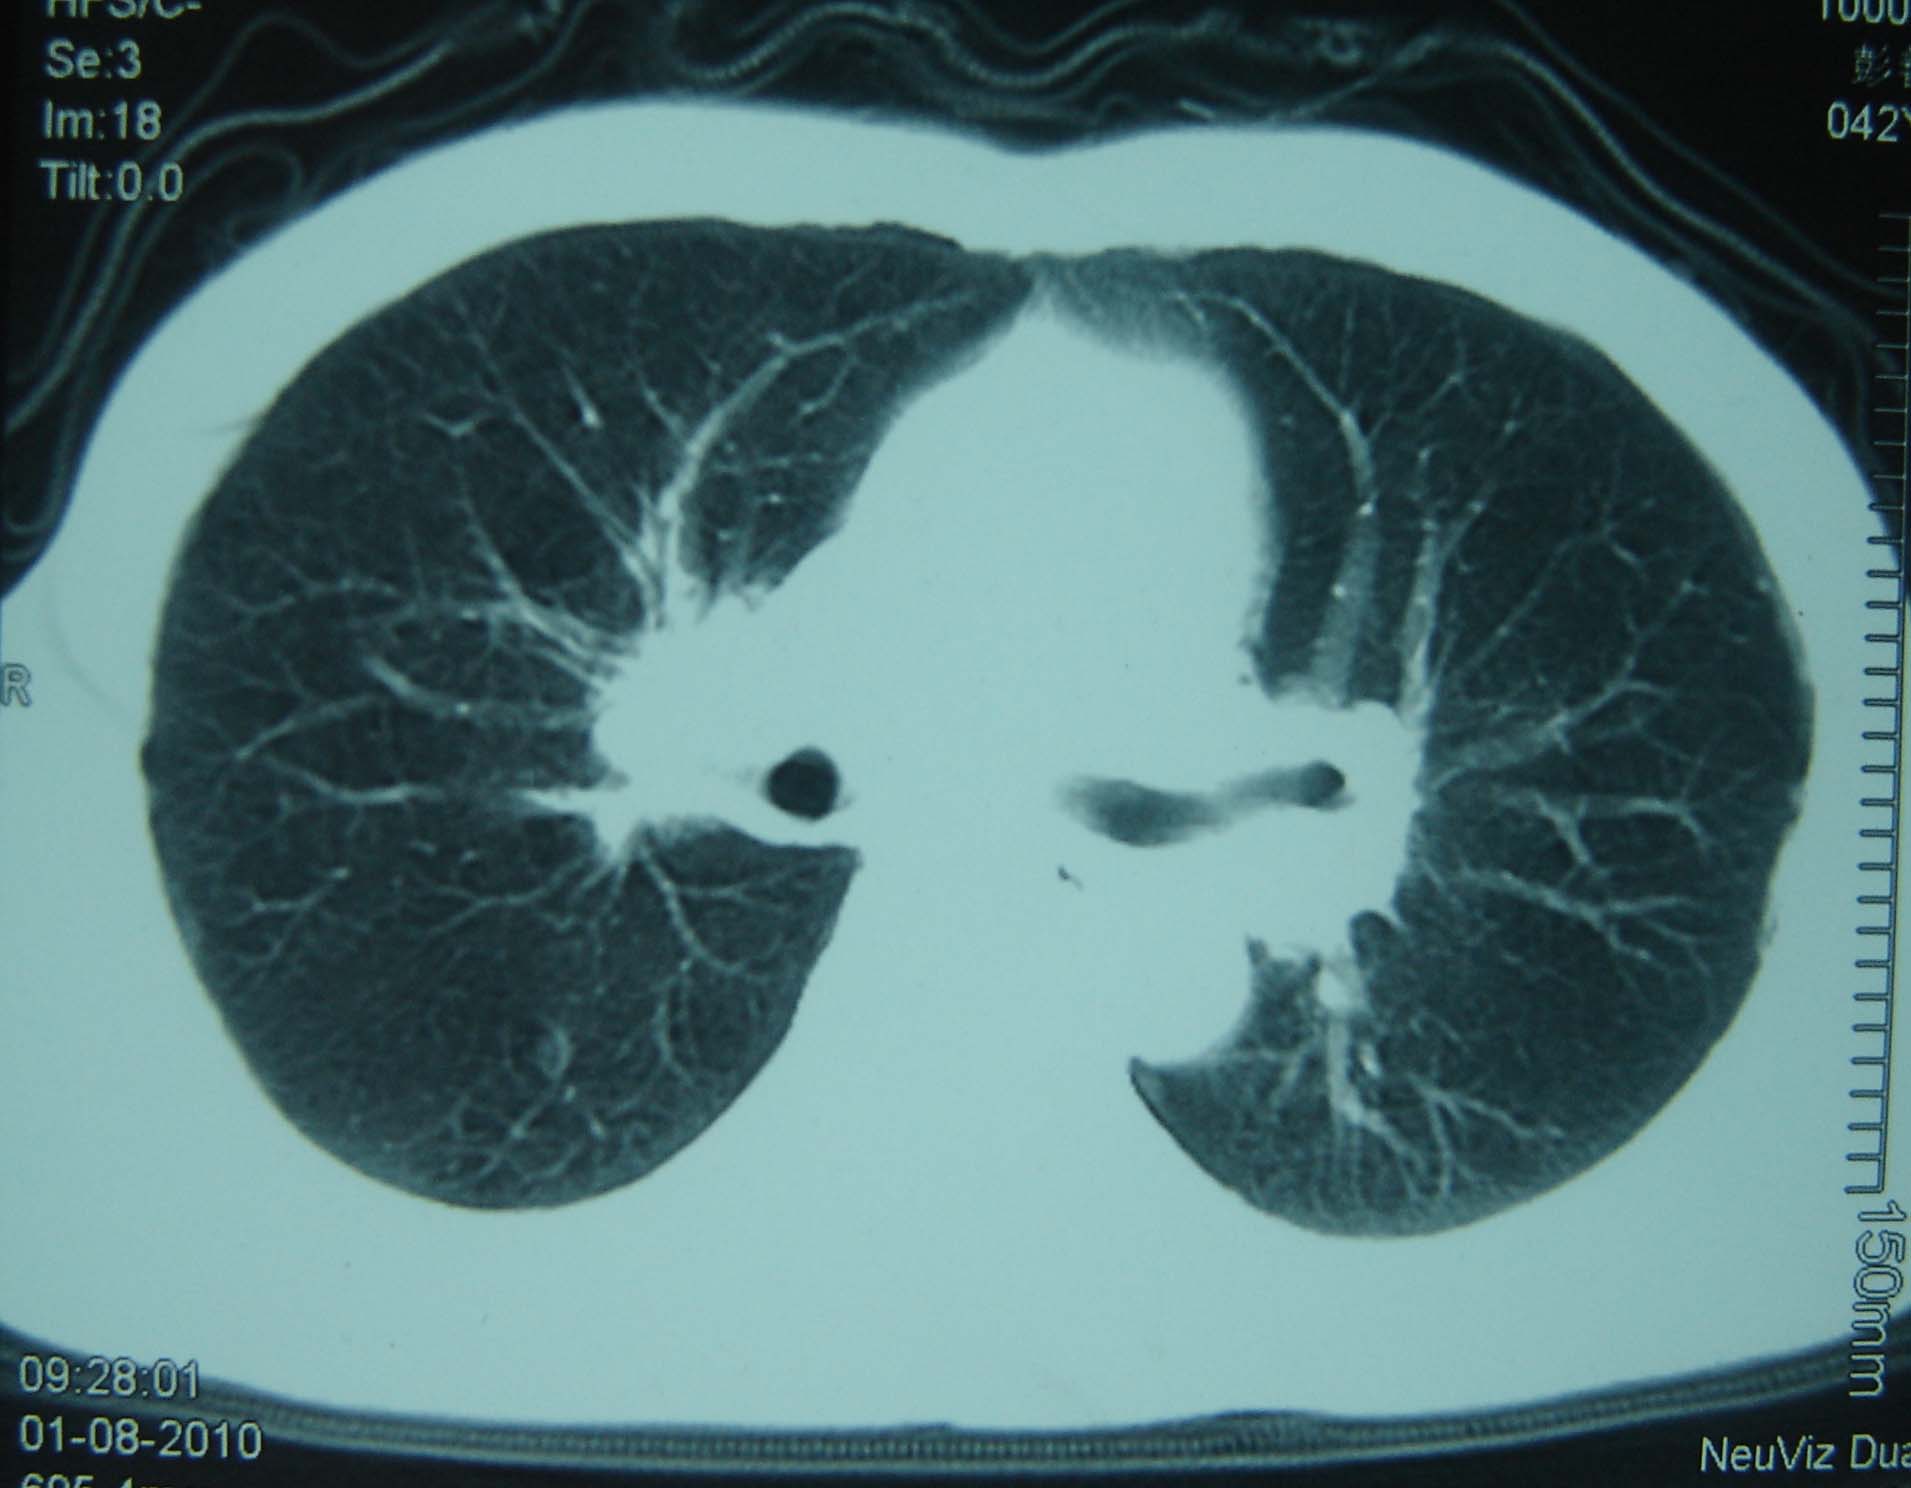

标题: CT25321:两肺多发结节 请会诊 [打印本页]

男 、43岁,咳嗽胸痛,装修工,平时接触粉尘较多,有吸烟史10多年,纤维支气管镜检查未发现异常,胃镜、腹部b超检查亦未发现异常,颈部淋巴结活检未发现肿瘤细胞。

不能排除转移,如果不能找到原发灶,只有短期随访。

结节病?转移瘤?

1)考虑双肺及胸膜多发性转移瘤。2)肺气肿。